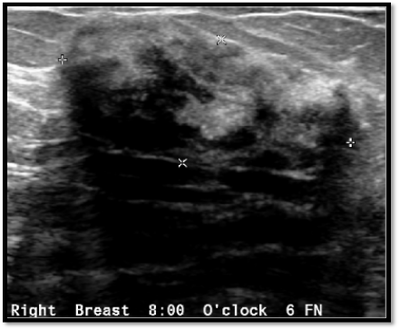

Breast Ultrasound

29 year old uniparous lady from Middle East presented with right breast lump...

Read More